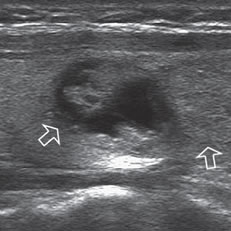

Un nódulo que tiene un componente quístico significativo, usualmente es un nódulo benigno hiperplástico, que ha acumulado abundante coloide (Figura 2a) o bien, un nódulo sólido que ha experimentado un proceso de degeneración colicuativa o hemorragia (Figura 2b). El coloide o el contenido líquido de un nódulo se ve anecogénico (negro en la imagen ecográfica) y las estructuras sólidas se ven ecogénicas (distintos tonos de grises), siendo la ecogenicidad similar al del parénquima tiroideo. En un nódulo sólido la ecoestructura y la ecogenicidad pueden ser variables. En general, la frecuencia de carcinoma es muy baja en nódulos quísticos13 y la mayoría de los carcinomas se presentan como nódulos sólidos (Figura 2c).

Figura 2. a) Quiste coloideo anecogénico y focos ecogénicos (flecha) con artefacto en cola de cometa; b) Nódulo mixto sólido-quístico (cabezas de flechas). Imagen vegetante (flecha) adherida a un tabique que se proyecta al lumen; c) Comparación entre el aspecto ecográfico de un cáncer papilar sólido (flecha abierta) y un quiste coloideo anecogénico.